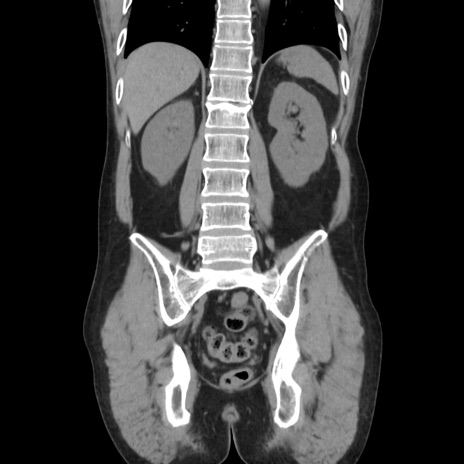

症例37(冠状断像)

【症例】40歳代 男性

【主訴】腹痛

【現病歴】4時間ほど前に電車に乗車中に臍部上より腹痛出現。徐々に増悪し起立困難となり、救急外来受診。生ものは数日食べていない。今朝お雑煮を食べた。

【身体所見】BT 36.8℃、BP 117/84mmHg、HR 91/min、SpO2 97%、苦悶様、腹部:臍上部広範囲圧痛あり、反跳痛±

【データ】WBC 8100、CRP 0.03

横断像